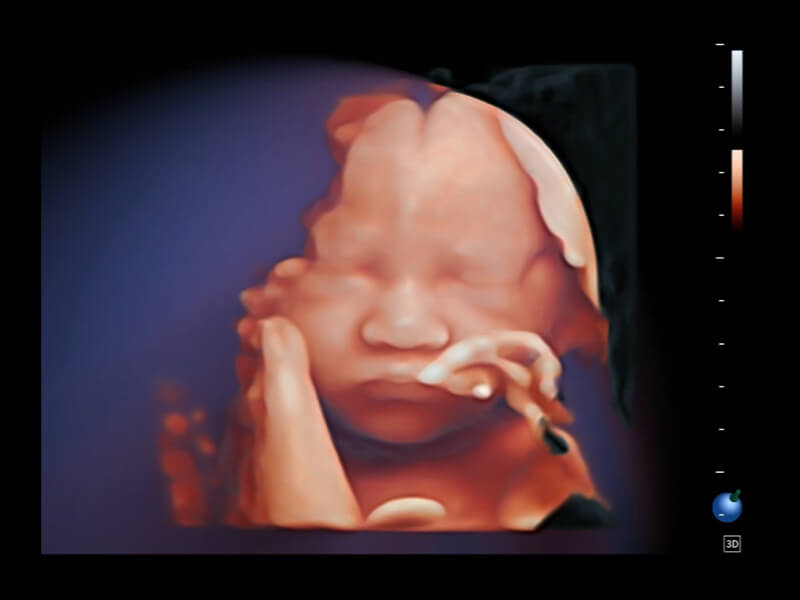

HD Portrait

S-Live Studio